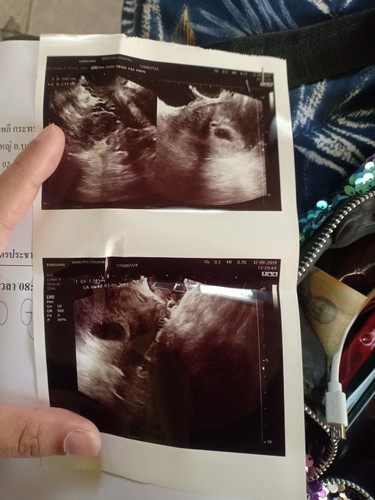

ท้องได้9สัปดาห์ซาวด์ไม่เจเสียงหัวใจเด็ก

ท้องได้9สัปดาห์ซาวทั้งหน้าท้องทั้งภายในไม่เห็นหัวใจเด็ก ถุงตั้งครรภ์ยังอยู่ดี เลือดในช่องคลอดไม่มี หมอให้เวลา2อาทิตย์เด็กต้องมา ถ้าไม่มาเป็นท้องลม มีสิทธิ์มากน้อยเเค่ไหน ใครเคยเจอปัญหานี้บ้าง

ในใบซาวของคุณแม่ 6 สัปดาห์ อยู่นะคะ อาจจะยังไม่เห็นตัวเด็ก แนะนำซาว คลีนิคอีกครั้งเพื่อความชัวร์นะคะ เราเจอตัวลูกตอน 8 สัปดาห์ค่ะ

เป็นกำลังใจให้คุณแม่นะคะ แอบเห็นในใบซาวด์อายุครรภ์6w++เองใช่มั้ยคะ น้องอาจจะตัวเล็กมากเลยยังไม่เห็นคะ